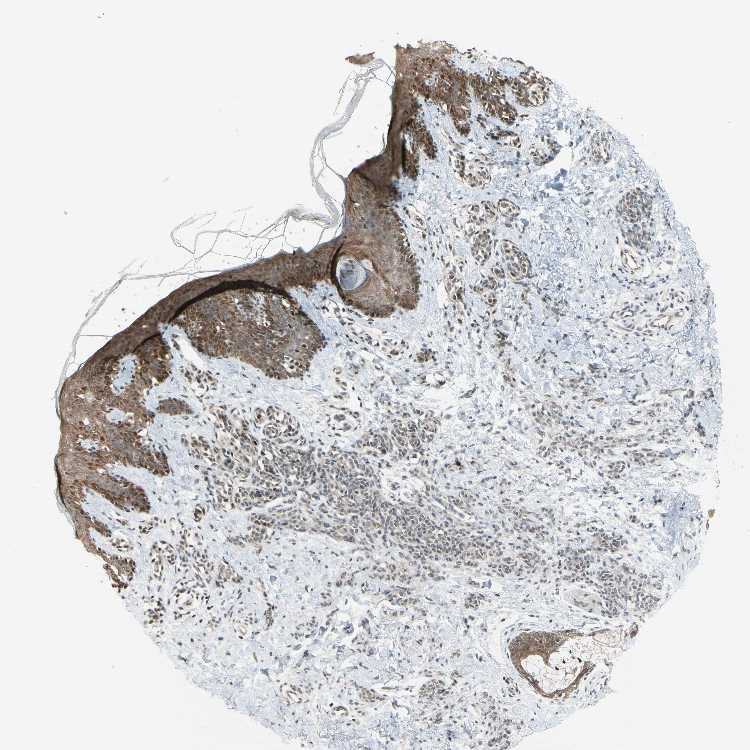

SKIN 2 - Antibody stainingi

Antibody staining in the annotated cell types in the current human tissue is reported as not detected, low, medium, or high, based on conventional immunohistochemistry profiling in selected tissues. This score is based on the combination of the staining intensity and fraction of stained cells.

Each image is clickable and will lead to virtual microscopy that enables deeper exploration of all samples and also displays staining intensity scores, fraction scores and subcellular localization as well as patient and tissue information for each sample.

Antibody CAB010824

Epidermal cells Medium